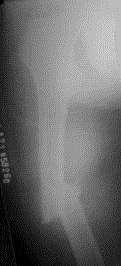

病历摘要: 患者×××,男性,34岁,车祸致伤右大腿后肿胀、疼痛、畸形,活动受限2小时。查体:右大腿肿胀,成角畸形,骨连续性中断,右足背动脉搏动存在,右足...

问题 病历摘要: 患者×××,男性,34岁,车祸致伤右大腿后肿胀、疼痛、畸形,活动受限2小时。查体:右大腿肿胀,成角畸形,骨连续性中断,右足背动脉搏动存在,右足伸屈功能正常。 关于股骨骨折畸形愈合的叙述下列哪些是正确的?

选项 A、成角畸形并短缩病例术前应做短期牵引 B、截骨矫正术常规要植骨 C、股骨干的成角畸形成人大于30°,儿童大于15°即应采取截骨矫正术 D、行截骨矫正术前因膝关节长时间固定而活动障碍,术前就锻炼展膝至90° E、最常见的畸形愈合是成角畸形,其次为短缩畸形及旋转畸形

答案 ABDE